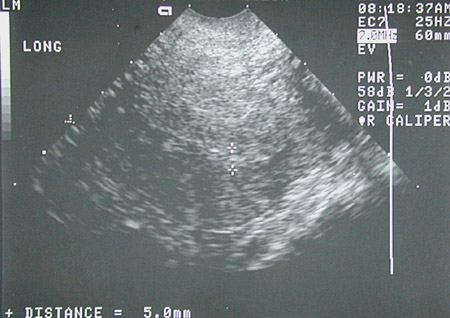

![]() | By transvaginal ultrasound in the view above, a ring-like structure is present in the right adnexal region, highly characteristic for an ectopic pregnancy because no gestational sac was present in the uterine cavity, as seen below, only a thickened endometrium. The beta-HCG was also elevated. |